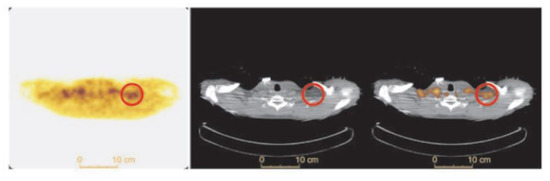

FTHA is a fatty acid probe that is transported into cells by fatty-acid transport protein gets trapped in the mitochondria after commitment to the mitochondrial fatty acid oxidation pathway [59]. It was initially developed to assess oxygenation of myocardium [59]. It has since been used by several groups to assess fatty acid uptake by BAT (Figure 7). Labbé and colleagues showed FTHA localizes to BAT as FDG does with cold stimulation in rodents [49,60]. FTHA actually identified additional periaortic and cervical BAT depots FDG did not manage to pinpoint [49]. Ouellet showed dynamic FTHA uptake over 30 min increases with in adult human iBAT with cold exposure using Patlak graphical analysis [28]. Dadson and colleagues found dynamic FTHA uptake over 15 min increased in iBAT after bariatric surgery in a cohort of morbidly obese women using graphical analysis with concomitant increase in CT radiodensity, indicating lower intracellular iBAT lipid stores [29].

Figure 7.

BAT FTHA uptake in a healthy human subject. Transverse FTHA-PET (left panel), CT (middle panel) and fused PET/CT (right panel) in a healthy subject after 1 h of cold exposure. Supraclavicular BAT is shown in the red circle. Image reproduced with permission from reference 28.